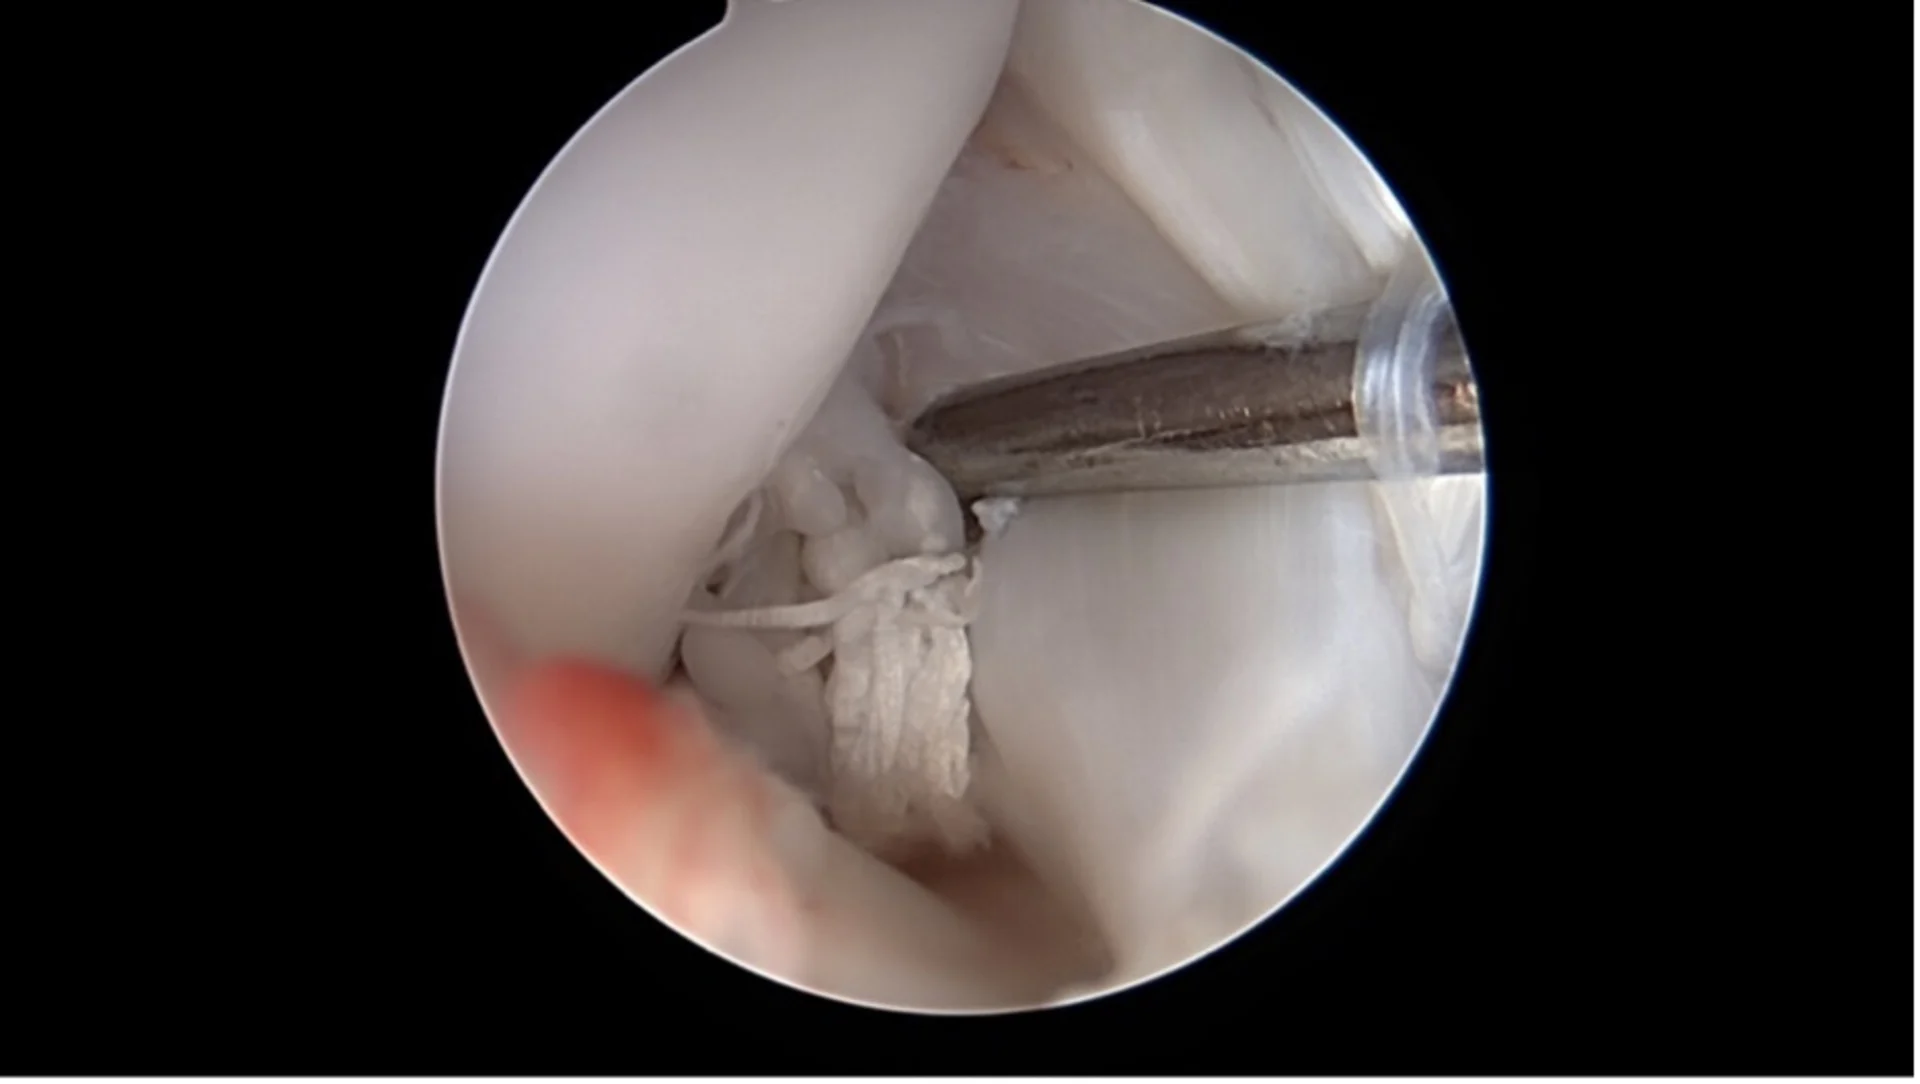

Nanoscopie

Encore plus fine que l’arthroscopie, la nanoscopie utilise des instruments très petits et une imagerie haute résolution dans l’articulation. Elle est particulièrement adaptée aux petits chiens. Les deux méthodes sont mini invasives, limitent le traumatisme tissulaire et favorisent une récupération plus rapide.

Arthroscopie

Une caméra miniaturisée permet de visualiser directement l’intérieur de l’articulation par de petites incisions cutanées. Les lésions du ligament croisé et les dommages associés comme les déchirures du ménisque peuvent être diagnostiqués et souvent traités immédiatement.